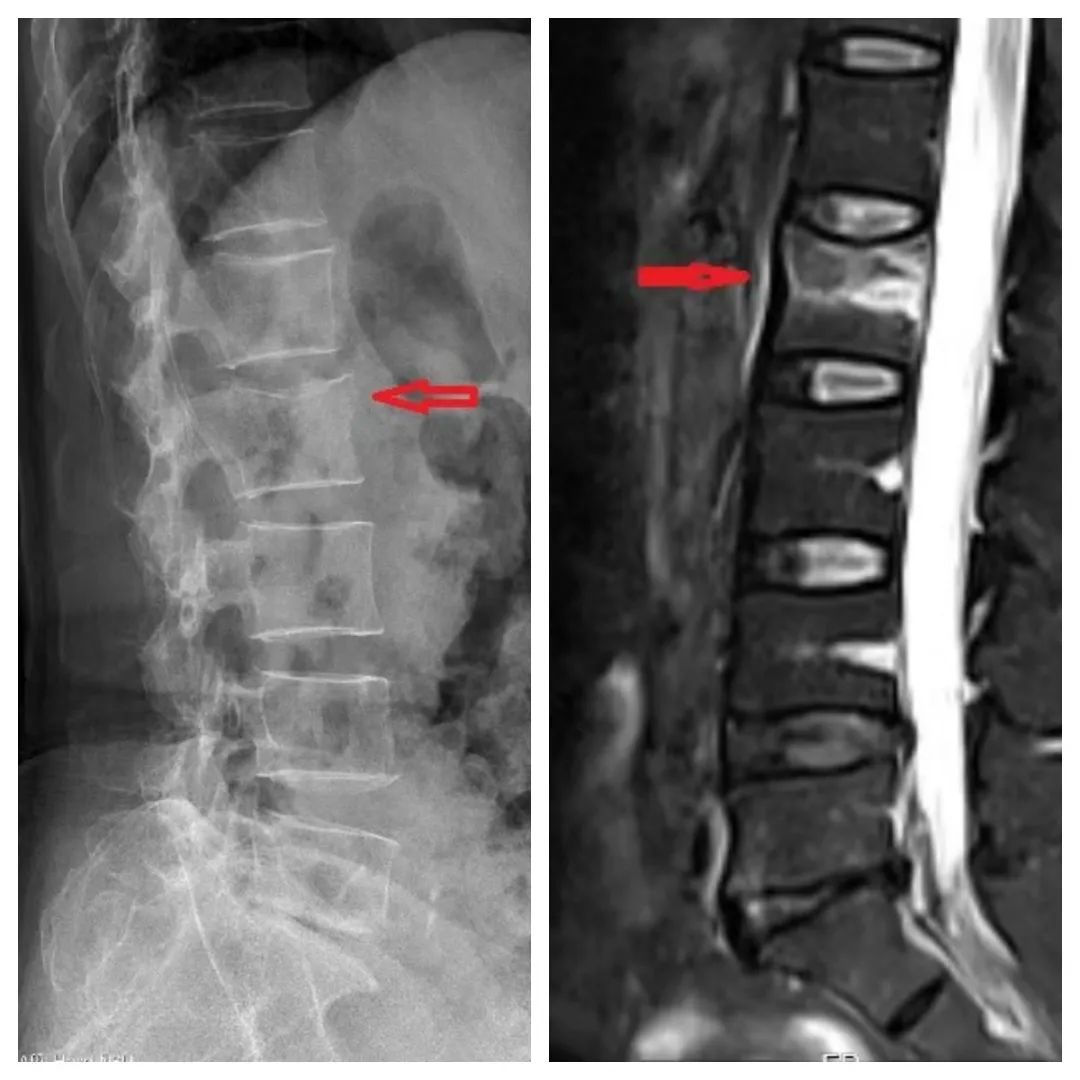

丁阿姨的X片(左)、磁共振(右),提示腰2椎体骨折

家人赶紧将其送到宁波大学附属第一医院。经检查,确诊为脊柱腰2椎体发生压缩性骨折。

如果保守治疗的话,丁阿姨需要卧床2-3个月。她选择接受微创椎体成形手术。通俗地说,在受伤椎体注入“骨水泥”来加固和帮助恢复。